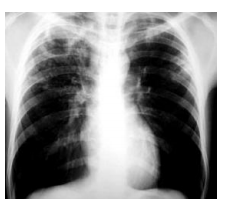

O diagnóstico provável nesse caso é